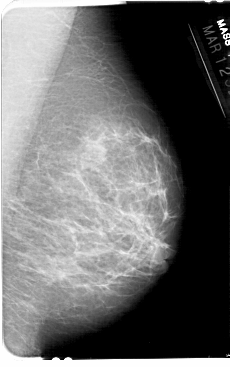

A_1607_1.RIGHT_MLO

RIGHT_MLO LINES 5491 PIXELS_PER_LINE 3436 BITS_PER_PIXEL 12 RESOLUTION 43.5 NON_OVERLAY